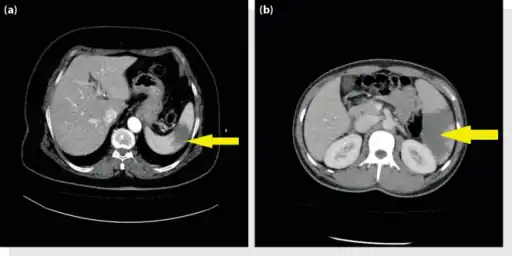

a, b) Splenic infarction.

An abdominal CT scan is the most commonly used modality to confirm the diagnosis,[3] although abdominal ultrasound can also contribute.[16][17][18]